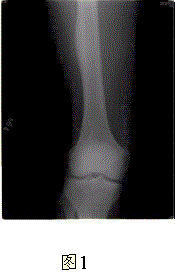

问题 患者男,17岁,右大腿外侧间歇性疼痛逐渐加重近3个月,夜间为重,X线片及CT示右股骨干下段外侧骨皮质梭形增厚硬化,增厚的骨皮质中心隐约可见小圆形低密度灶,骨髓腔未闭合,无外伤史(图1、2)。 最可能的诊断是

选项 A.成骨细胞瘤 B.骨软骨瘤 C.骨样骨瘤 D.骨肉瘤 E.非骨化性纤维瘤

答案 C